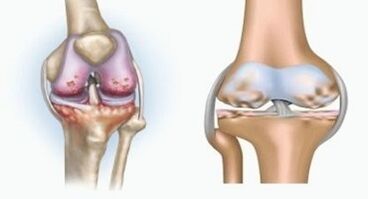

Both pathologies affect joints, but differ in the nature of change.

With arthritis

Arthritis is an inflammation of the connective tissue - a sinum membrane that contains many vessels and provides lymph flow.The inflammatory process leads to violation of the diet of articulated tissues, as a result of which the production of articulated lubrications - Sinovian liquid is limited.

With arthrosis

Arthrosis is a degenerative-dystrophine process associated with the destruction of tissue cartilage wrists.The rink is gradually destroyed, dry, the distance between the bones of the joint decreases, which is the cause of pain.In severe forms, destruction affects bones.They become porous, lose density, become fragile.

For example, what is the difference between arthritis and the arthrosis of the knee wrist?In addition to arthritis, Sinovi shell of articulated tissues.This causes an increase in temperature in the compound.

Shared swollen, it develops a persistent pain syndrome, intensification during the movement.In addition to arthrosis, pain occurs only after physical activity, you can hear the characteristic mater or clicks in the compound, a gradual compound is deformed and loses mobility.